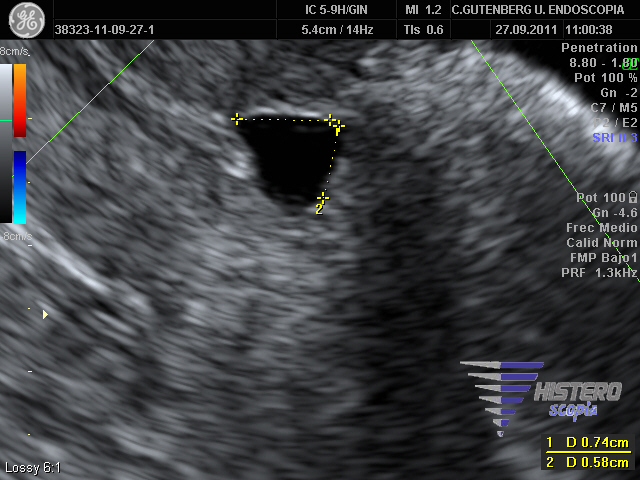

istmocele 2 istmocele 5 istmocele 3

istmocele 4 shot0140 istmocele 6